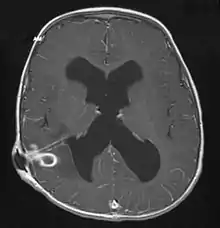

MRI (T1 with contrast) showing the ring-enhancing lesion. From a rare case report of an abscess formed as a complication of the CSF shunt. Jamjoom et al., 2009.[1]

The diagnosis is established by a computed tomography (CT) (with contrast) examination. At the initial phase of the inflammation (which is referred to as cerebritis), the immature lesion does not have a capsule and it may be difficult to distinguish it from other space-occupying lesions or infarcts of the brain. Within 4–5 days the inflammation and the concomitant dead brain tissue are surrounded with a capsule, which gives the lesion the famous ring-enhancing lesion appearance on CT examination with contrast (since intravenously applied contrast material can not pass through the capsule, it is collected around the lesion and looks as a ring surrounding the relatively dark lesion). Lumbar puncture procedure, which is performed in many infectious disorders of the central nervous system is contraindicated in this condition (as it is in all space-occupying lesions of the brain) because removing a certain portion of the cerebrospinal fluid may alter the concrete intracranial pressure balances and causes the brain tissue to move across structures within the skull (brain herniation).

Ring enhancement may also be observed in cerebral hemorrhages (bleeding) and some brain tumors. However, in the presence of the rapidly progressive course with fever, focal neurologic findings (hemiparesis, aphasia etc.) and signs of increased intracranial pressure, the most likely diagnosis should be the brain abscess.